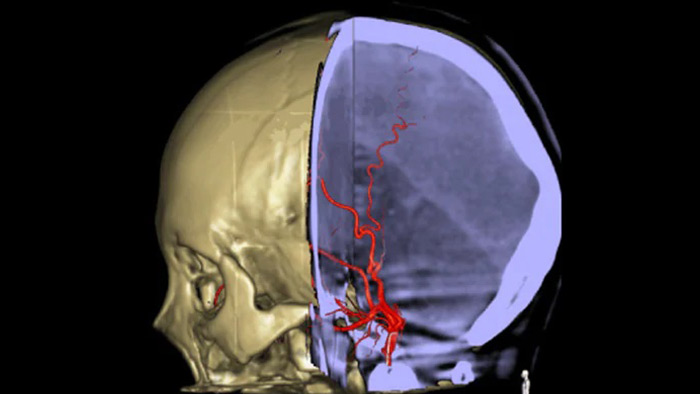

SmartCT Vaso позволяет проводить визуализацию за пределами тромба с помощью перипроцедурного создания изображений дистальных сосудов при ишемическом инсульте. SmartCT Vaso — это метод сбора данных, основанный на получении КТ-изображений с помощью конического пучка и внутриартериальной инъекции контраста. Технология позволяет проводить визуализацию за пределами тромба с помощью перипроцедурного создания изображений дистальных сосудов при ишемическом инсульте. При ретроградном наполнении становится видна структура сосудов до и после тромба. 3D-схема сосудов SmartCT Vaso может использоваться при визуализации устройств для извлечения тромба.

Технология SmartCT Roadmap предоставляет данные изображений анатомических структур, обеспечивая точность навигации при проведении к тромбу проводника, катетера и специального устройства.